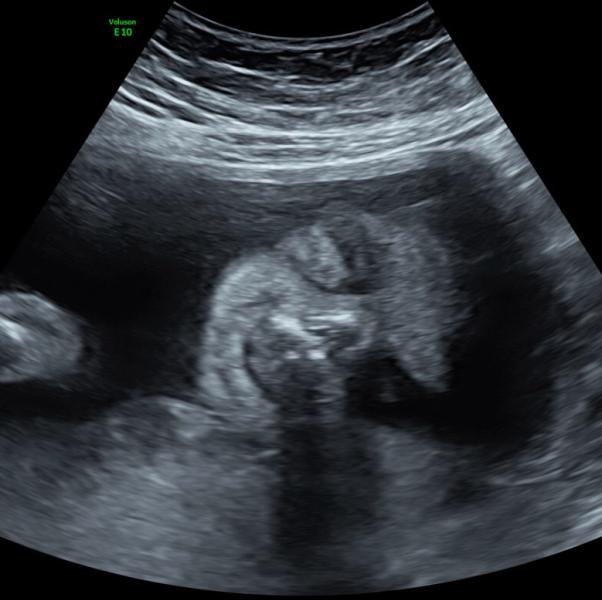

People Asking Me Is This Really My Ultrasound Like Yes It Is , This Is My Daughter. Tooken By My UT at my hospital/ At my high risk appointment. Please do not use or claim her as yours . Thanks 😀

Thank you! I'm patiently waiting for her to come, a week left